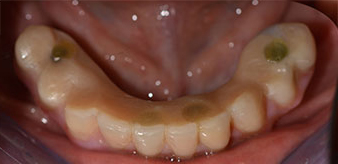

The 64-year-old patient presented with residual dentition of teeth 38, 33 and 43 and a clasp denture in the mandible (Fig. 1 and 2).

residual dentition

Fig. 1